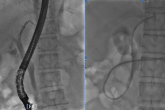

ERCP技术

ERCP中文名称:经内镜逆行胰胆管造影术。该技术的原理是在十二指肠镜直视下插入造影导管至十二指肠主乳头,进行X线下造影,显示胆管及胰管病变,并可进行胆管取石、病检、引流胆汁、安置支架的技术,是一项经口内镜胆道治疗技术。ERCP治疗的疾病包括1.胆总管结石、胆道术后残余结石和复发结石;2.各种原因所致的阻塞性黄疸;3.失去手术机会的胆管肿瘤及胰头肿瘤患者通过ERCP放置胆道支架可以减轻黄胆,改善生活质量;4.胆源性胰腺炎,经ERCP可解除胰腺炎病因,有效提高胆源性胰腺炎治愈率;5.急性化脓性胆管炎;胆道蛔虫症;奥狄氏括约肌狭窄;6.术后胆漏;7.胆道狭窄。ERCP治疗的特点1.该技术无需开腹手术,体表无伤口,无切口感染风险;2.大部分患者无需全身麻醉;3.手术操作时间短,患者治疗后即可活动,更适宜不